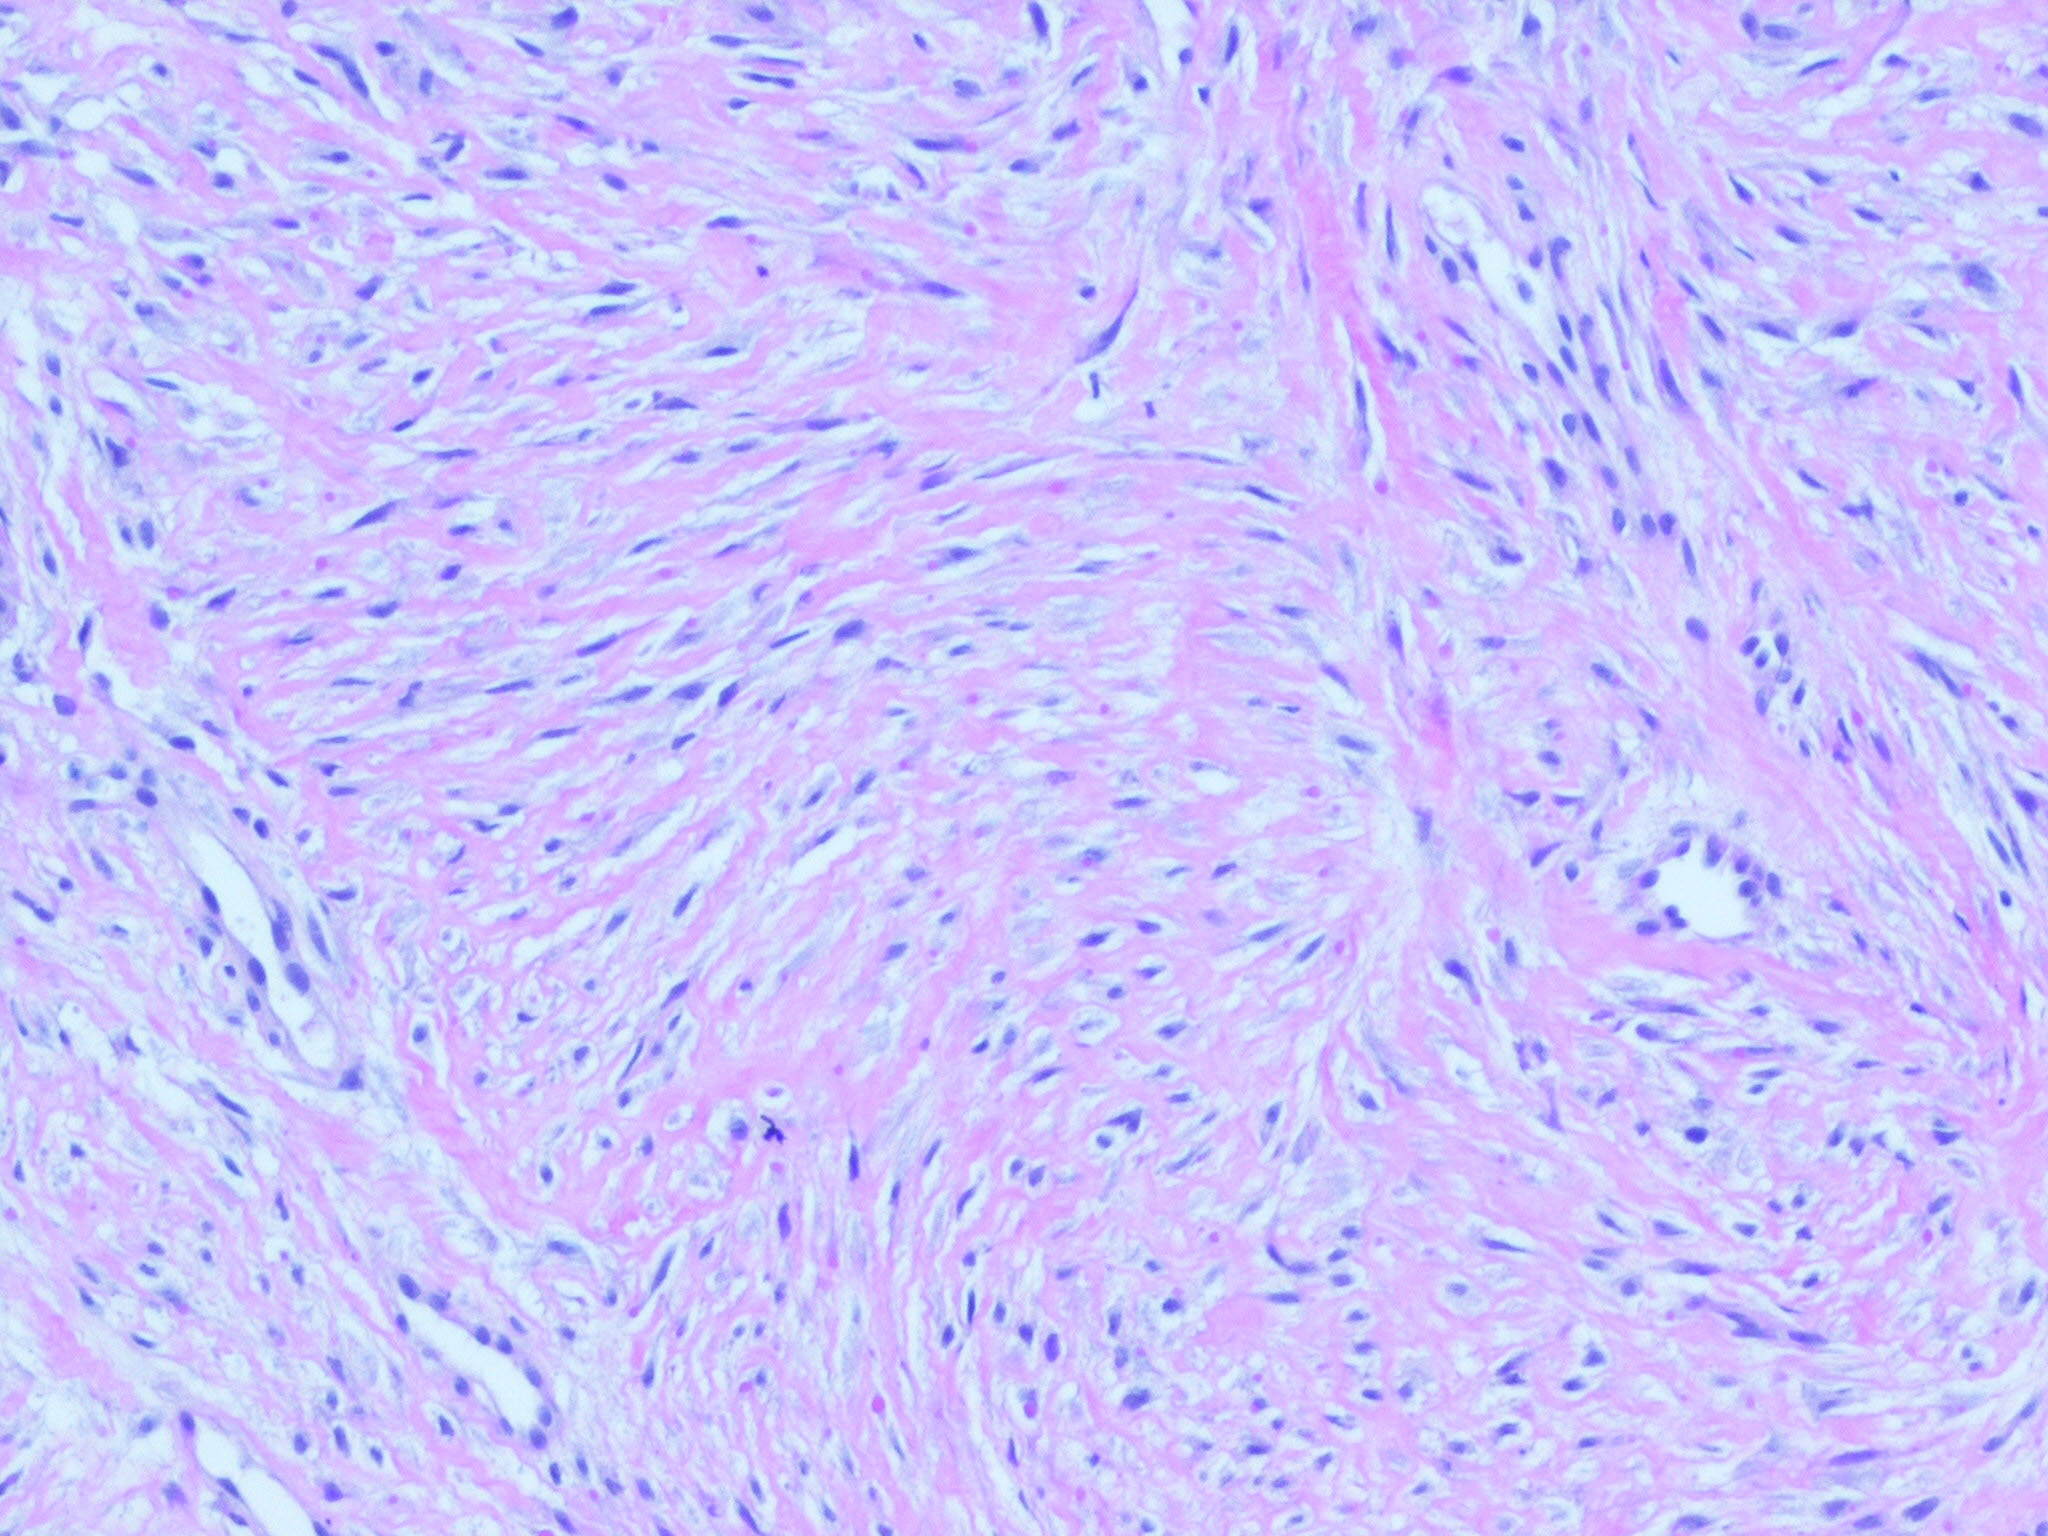

Infantile digital fibroma = الليفوم على الاصبع الطفلي